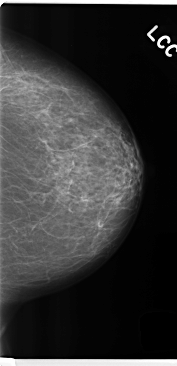

C_0278_1.LEFT_CC

LEFT_CC LINES 4752 PIXELS_PER_LINE 2296 BITS_PER_PIXEL 12 RESOLUTION 50 NON_OVERLAY